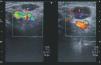

Niña sana de 6 años con tumefacción dolorosa inguinal izquierda de 3 días de evolución y febrícula. Presenta 2 tumoraciones inguinales muy dolorosas y calientes. El resto de la exploración así como el estudio analítico es normal. En la ecografía inguinal se observan: adenopatías de tamaño significativo, muy hipoecogénicas y muy vascularizadas (hipervascularización de carácter central), dos de gran tamaño localizadas en tejido celular subcutáneo, adyacentes y anteriores a los vasos femorales comunes y al cayado de vena safena mayor (fig. 1). Con el diagnóstico de adenopatía inguinal izquierda reactiva a forúnculo en rodilla izquierda, se inicia tratamiento con amoxicilina-ácido clavulánico intravenosa 100 mg/kg/día. A los 5 días aunque la fiebre ha desaparecido, las adenopatías inguinales han aumentado de tamaño y se constata salida de material purulento por la pápula de la rodilla izquierda.

Figura 1.Estudio ecográfico: adenopatías de tamaño significativo, muy hipoecogénicas y muy vascularizadas (hipervascularización de carácter central), dos adenopatías de gran tamaño localizadas en tejido celular subcutáneo, adyacentes y anteriores a los vasos femorales comunes y al cayado de vena safena mayor, la mayor de 2 1,3 cm.